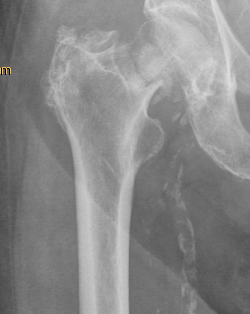

Ursache für komplexe Knochenbrüche wie Hüft- oder Schulterfraktur ist eine reduzierte Knochenqualität. Die häufigsten dieser Verletzungen sind die handgelenknahe Speichenfraktur (Radiusfraktur), die hüftgelenknahe Oberschenkelfraktur (mediale/pertrochantäre Fraktur), die Schulterfraktur (proximale Humerusfraktur) oder die Fraktur eines oder mehrerer Wirbelkörper.

Diese Verletzungen können für einen älteren Menschen teilweise gravierende Folgen haben. Eine Schenkelhalsfraktur kann bei einem älteren Patienten mit dem plötzlichen Verlust seiner Selbstständigkeit und Mobilität verbunden sein und eine Vielzahl anderer Komplikationen nach sich ziehen. Eine drohende temporäre oder dauerhafte Pflegebedürftigkeit kann sich daraus entwickeln.